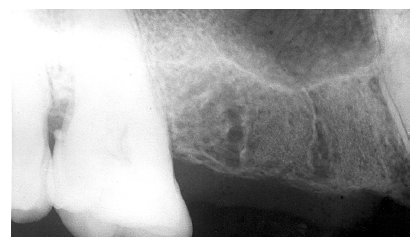

Figure 3 - Dentin Caries

Figure 3

Dentin caries extends into the tooth dentin and can be recognized by noting the focal loss of dentinal radiopacity. Most commonly, this darkened dentin is located beneath carious enamel and, typically, the lateral dimension of the dentinal involvement exceeds that of the associated enamel caries (Figure 3). Dentin caries may be discerned interproximally, on the occlusal surface, buccally/lingually, or on root surfaces.

Incipient occlusal dentin caries may be difficult to identify on radiographic images and root caries must be carefully distinguished from cervical burnout, as we will discuss later.